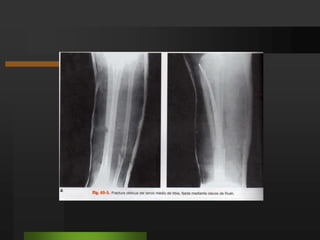

Osteosíntesis con placa y tornillosSu uso depende del tipo de fractura.En casos que existe pérdida de sustancia ósea o retardo de la consolidación Adicionar injerto óseo al foco.Fracturas con algunos fragmentos grandes. Se combina la placa de osteosíntesis con tornillos suplementarios para fijación ósea en otros planos del espacio

Osteosíntesis con placay tornillosSu uso depende del tipo de fractura.En casos que existe pérdida de sustancia ósea o retardo de la consolidación Adicionar injerto óseo al foco.Fracturas con algunos fragmentos grandes. Se combina la placa de osteosíntesis con tornillos suplementarios para fijación ósea en otros planos del espacio